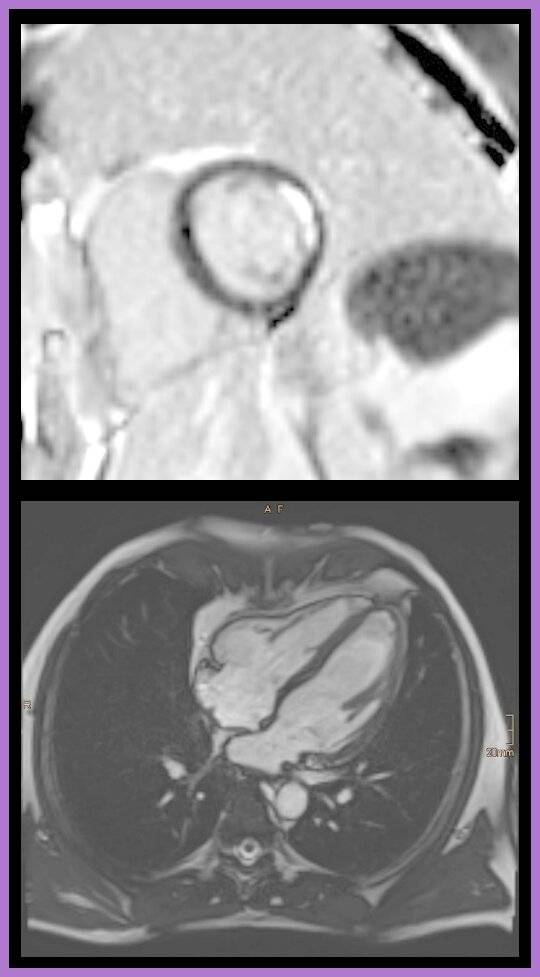

Abb A: MRT eines Fetus im Mutterleib mit einem Aufstau des Hirnwassers und erweiterten Hirnkammern. Abb B: MRT des Herzens nach einem Herzinfarkt, die Narbe ist im oberen Bild hell abgrenzbar (Pfeil) Abb C: Herz-CT mit Darstellung der Herzkranzgefäße, die einliegenden Gefäßstützen (Stents) sind sehr gut einsehbar (Pfeile)